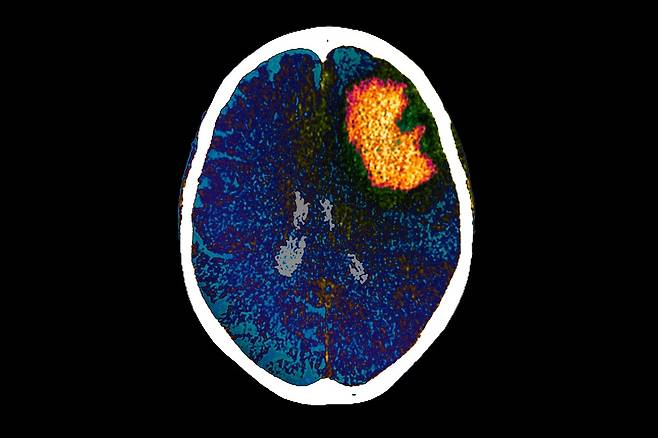

| ▲ 장기적인 의식 상실로 이어질 수 있는 손상인 뇌출혈(주황색, 인공 색상 처리된 이미지)이 있는 환자의 뇌) |

| ⓒ Science Photo Library |

뇌는 겉으로는 조용해 보여도 내부에서는 회복을 준비하고 있었던 것이다. 이는 또렷한 수면 방추가 의식 회복을 예측할 수 있는 조기 신호로 활용될 수 있음을 의미한다. 연구진은 WFSS와 CMD 모두 회복 가능성을 예측하는 독립적인 단서로 작용하며, 둘을 함께 분석할 경우 예측력이 더 높아진다고 밝혔다.